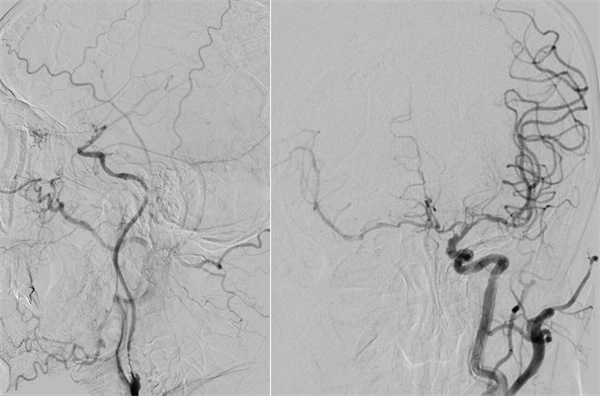

患者高先生,70岁,患有高血压病多年。2年前曾行冠状动脉搭桥术,平素规律服药。2个月前,他因左上肢突然麻木被送至清华大学垂杨柳医院急诊科就诊。头颅CT提示右侧顶叶少量蛛网膜下腔出血。后入住神经外科进一步诊治,全脑血管造影(DSA)结果显示:右侧椎动脉起始部重度狭窄约70%,左侧椎动脉颅内段闭塞;右侧椎动脉颅内段存在大小约3.5×2毫米的夹层动脉瘤;右侧颈内动脉颅外段存在重度狭窄,左侧颈内动脉通过前交通动脉代偿。

▲右侧颈内动脉颅外段重度狭窄,左侧颈内动脉代偿右侧颅内